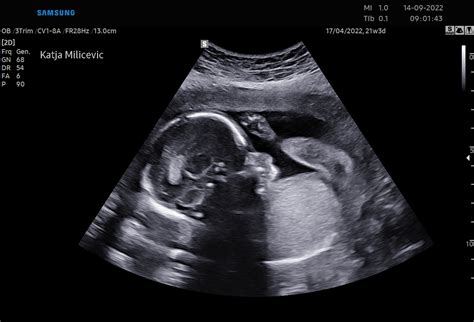

Prvi trimester je obdobje številnih pomembnih pregledov, ki zagotavljajo spremljanje zdravja matere in otroka. Med temi pregledi sta ključna ultrazvočna potrditev nosečnosti do 11. tedna in pregled nuhalne svetline, ki se običajno opravi med 11. in 14. tednom nosečnosti. Nuhalna svetlina je neinvazivna ultrazvočna preiskava, ki lahko oceni tveganje za kromosomske nepravilnosti ploda, kot je Downov sindrom. Poleg ultrazvoka se v prvem trimestru izvajajo tudi laboratorijske analize krvne slike, krvnega sladkorja na tešče, krvne skupine in RH faktorja, ter testi na okužbe, kot sta toksoplazmoza in sifilis.